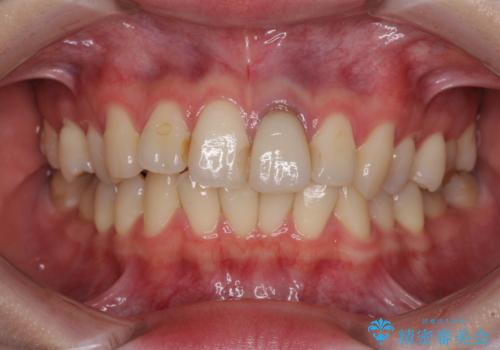

- 前歯のクラウン付近の歯肉が黒く見えることを気にして来院された患者様です。

根管治療を行った後に、オールセラミッククラウンにて補綴することとしました。